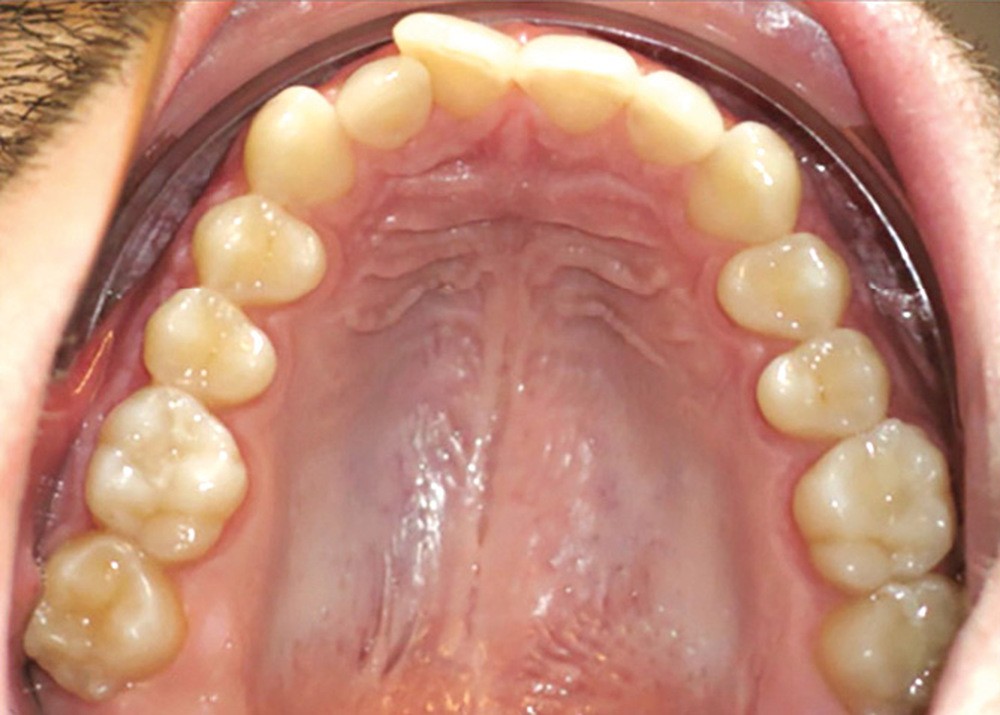

Examen endobuccal (fig. 2a-e)

L’arcade maxillaire est asymétrique, en hémi-lyre droite. Elle présente une mésio-position du secteur 1 en lien avec un encombrement antérieur estimé à 4 mm, se traduisant par une palato-position de la 12 et une rotation de la 11. On observe également des mésio-rotations des premières molaires et une palato-version incisive. L’arcade mandibulaire est ellipsoïde et présente un léger encombrement incisif (1 mm).

Concernant les relations occlusales, on observe une classe II complète subdivision droite. Le surplomb est absent et le recouvrement augmenté, estimé à 4 mm, a provoqué une usure des bords libres de 11 et 21 par attrition. Dans la dimension transversale, on constate une endoalvéolie maxillaire, ainsi qu’une concordance des médianes incisives entre elles, mais toutes deux déviées à droite par rapport au plan sagittal médian.